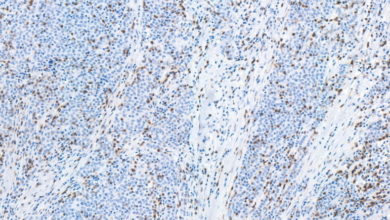

HealthScientists Uncover Anti-Inflammatory Strategies to Fight Cancer

After years of advanced trials and experiments, scientists have now revealed a new exciting discovery that shows how targeting inflammatory cells could slow down cancer growth and spread and could even be prevented if done in the earliest stages.